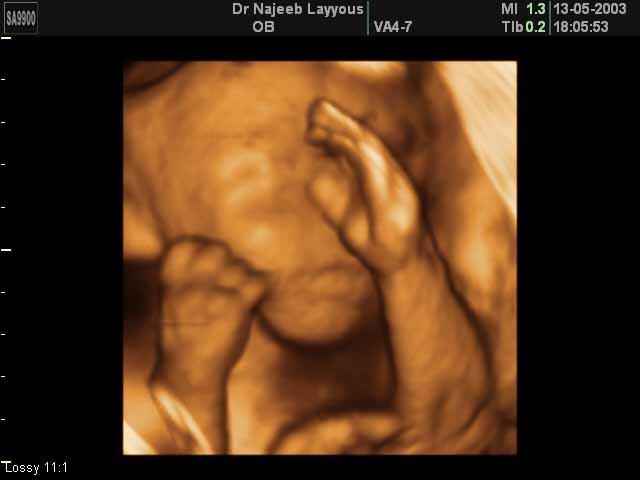

3D Ultrasound Scan Photos of Fetal Limbs | Dr N Layyous

3D Fetal Limbs Ultrasound Scan Photos